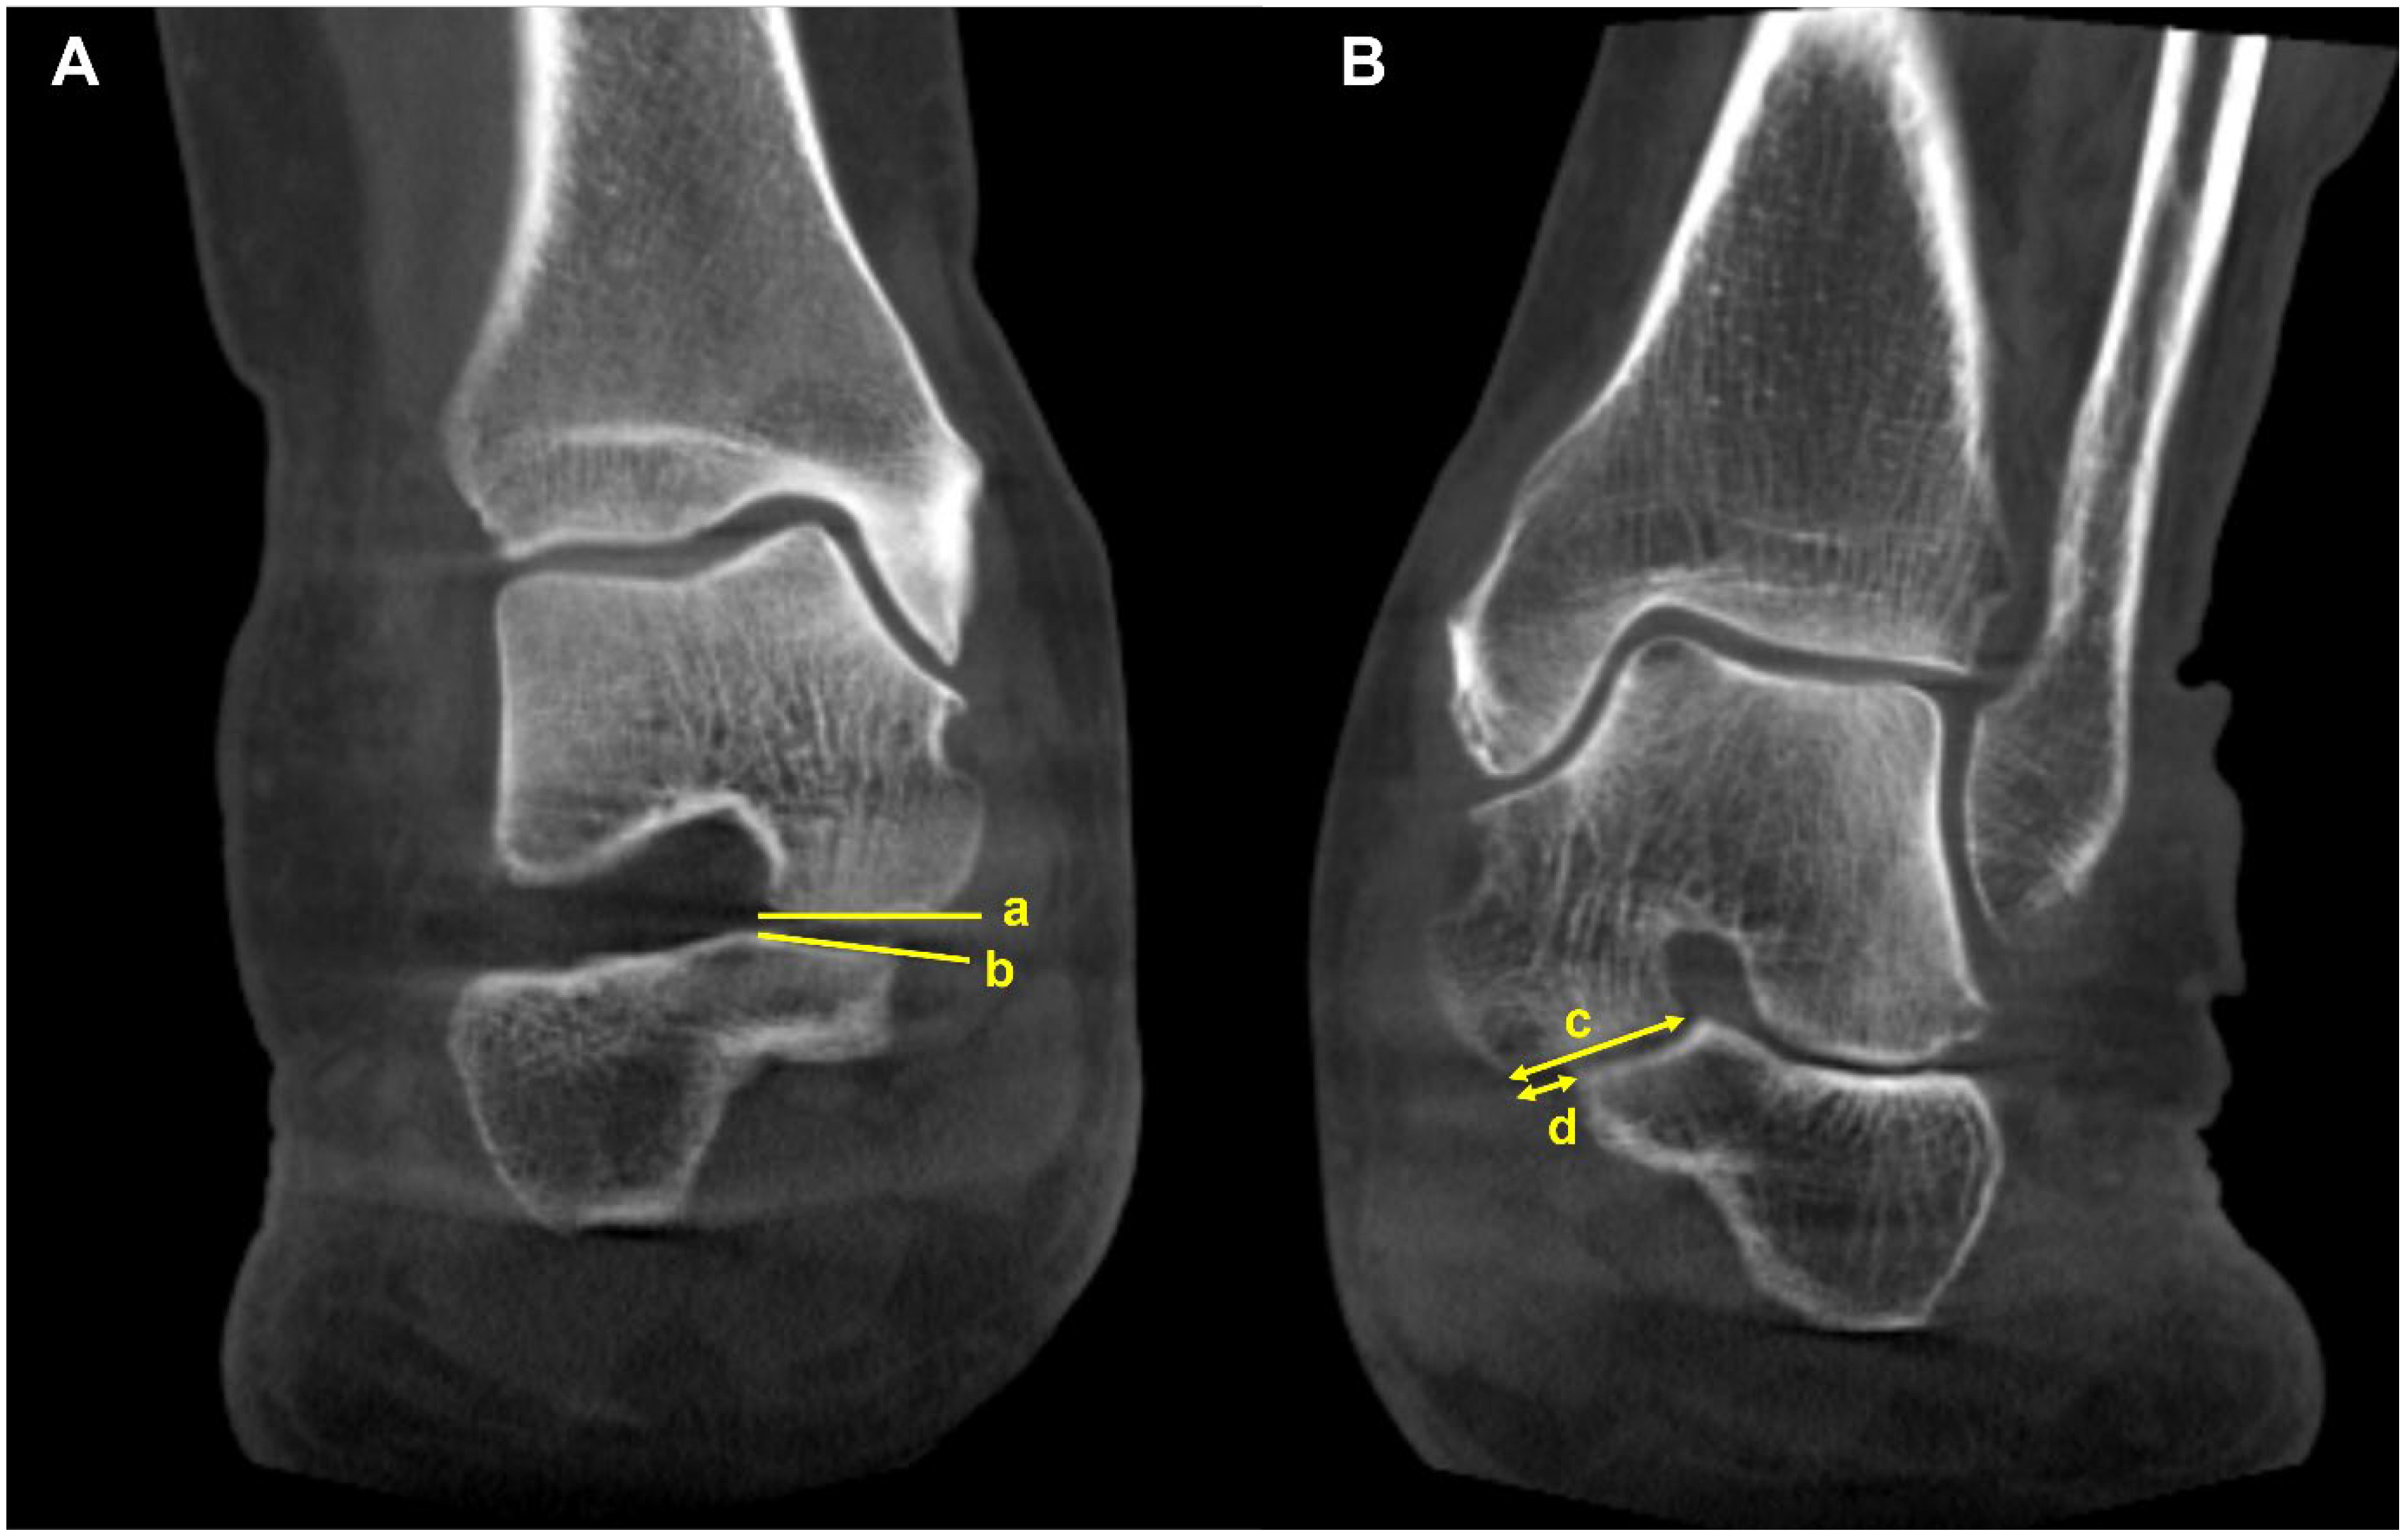

4.4. Peritalar Subluxation (Class D)

Peritalar subluxation is known to be a key pathological index in PCFD. It defines the complex 3D distortion that occurs in PCFD and is characterized by subluxation of the hindfoot through the triple joint complex [46]. The percentage of middle facet subluxation (MFS) and incongruence angle are considered validated markers for peritalar subluxation measured in WBCT [46]. Assessed at the midpoint of the subtalar joint middle facet in the sagittal plane, uncoverage of the middle facet on a coronal plane image is measured. Then, the percentage of MFS is measured by dividing the uncoverage of the middle facet by the width of the talar middle facet. The incongruence angle is the angle between both articular surfaces at the midpoint of the middle facet of the subtalar joint (Figure 11). De Cesar Netto et al. reported that an incongruence angle of >8.4° and an MFS percentage of >17.9° were found to be highly diagnostic for symptomatic stage II adult-acquired foot deformity [46]. The authors also compared the amount of subluxation of the middle and posterior facets of the subtalar joint to identify the superior marker to detect early peritalar subluxation [47]. They reported significantly pronounced subluxation of the middle facet than that of the posterior facet by an average of 17.7%, which implies that MFS may present an earlier and more significant sign of progressive peritalar subluxation.

Figure 11.

Middle facet subluxation. (A) Measurement of the incongruence angle of the middle facet of the subtalar joint on a coronal-plane weight-bearing CT image, which is an angle between both articular surfaces (a and b). (B) Measurement of the percentage of “uncoverage” of the middle facet of the subtalar joint on a coronal-plane weight-bearing CT image. (c) = the width of the talar middle facet, and (d) = the linear measurement of the middle facet uncoverage. The percentage of uncoverage of the middle facet of the subtalar joint = (d/c).

Subfibular impingement is also one of the findings characterizing peritalar subluxation in PCFD. To address this, Jeng et al. devised a calcaneofibular distance measured on the WBCT coronal view (Figure 12) [48]. The calcaneofibular distance is defined as the closest distance between the lateral aspect of the posterior facet of the calcaneus, which is the most reproducible point to measure from the calcaneus lateral wall and the fibula. Using this method, Kim et al. observed that subfibular impingement detected on the WBCT correlated best with HMA in the weight-bearing radiograph [43]. They also added that HMA cutoff values of 25.4 mm and 38.1 mm would be useful for ruling out and diagnosing calcaneofibular impingement, respectively.

Figure 12.

Calcaneofibular distance is the shortest distance from the fibula to the lateral margin of the posterior facet of the calcaneus in the coronal image (asterisk).